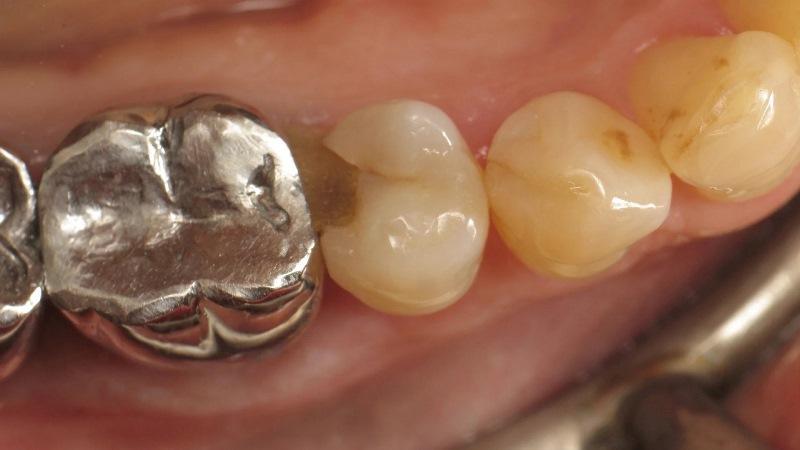

Наконец, была проведена легкая полимеризация в течение 20 секунд с мощностью ≥ 1000 МВт/см2 (фото 14). Затем было выполнено окрашивание светополимеризующимся тонированным композитом (FinalTouch, оранжевый; VOCO; фото 15). После 20 секунд полимеризации материала для определения характеристик (фото 16), был нанесен глицериновый гель (фото 17) а затем была проведена окончательная полимеризация (фото 18). Затем излишки были удалены, а поверхность отполирована (фото 19). Для корректировки прикуса использовалась артикуляционная бумага, чтобы визуализировать точки соприкосновения (фото 20) и внести необходимые коррективы (фото 21). Конечный результат получился очень естественным (фото 22).

Фото 20: Проверка окклюзии перед корректировкой.

Фото 21: Проверка окклюзии после корректировки.